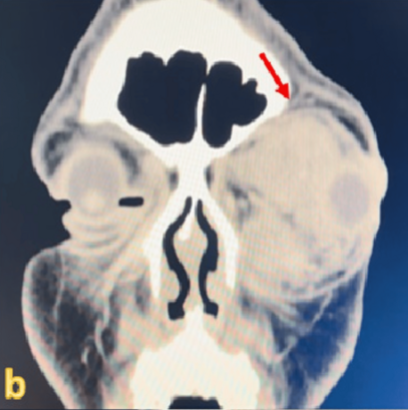

사진=Cureus 캡처.

첫 번째 환자는 31세 남성이다. 그는 11년 전부터 눈이 조금씩 튀어나왔지만, 통증이 없어 치료하지 않았다.

최근 눈을 다치면서 통증과 부기가 심해졌고, 그제야 병원을 찾았다. 당시 남성의 시력은 빛도 구분하지 못할 정도로 손상돼 있었다.

CT 촬영 결과, 시신경을 심하게 누르고 있는 큰 종양이 발견됐다. 이후 제거 수술을 받았으나, 이미 손상된 시신경은 회복되지 않았다.